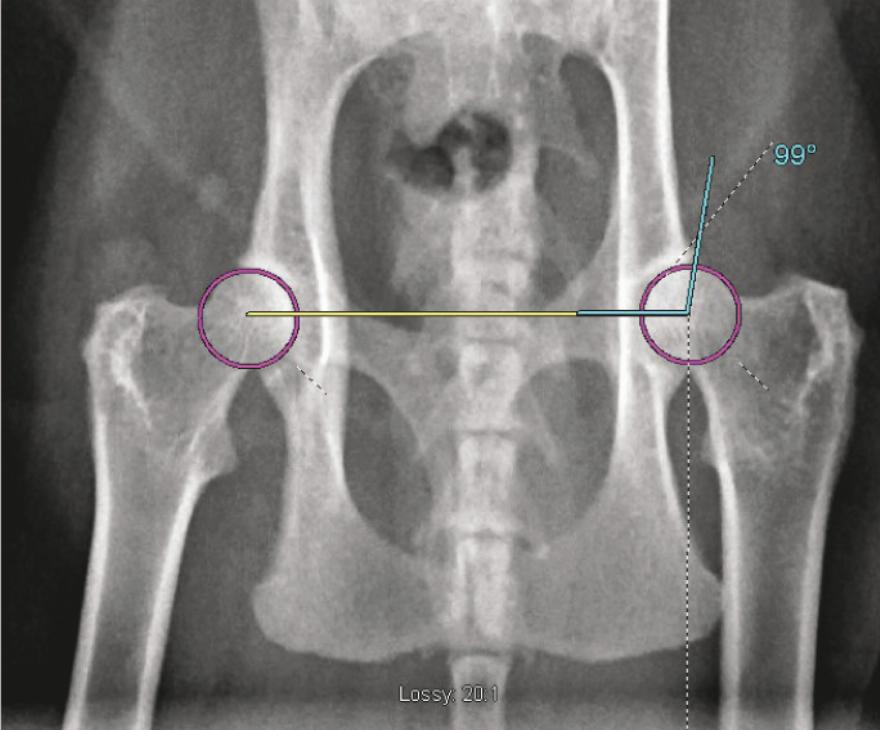

Εάν υποψιάζεστε ότι η γάτα σας πάσχει από δυσπλασία του ισχίου, είναι καλύτερο να επισκεφθείτε τον κτηνίατρό σας για να επιβεβαιώσετε το πρόβλημα. Αφού παρατηρήσετε συμπτώματα δυσπλασίας του ισχίου στη γάτα σας, ο κτηνίατρός σας μπορεί να θέσει επίσημη διάγνωση μετά από ακτινογραφία της πάσχουσας άρθρωσης.

Ο κτηνίατρός σας θα διαγνώσει τη δυσπλασία του ισχίου της γάτας σας μέσω φυσικής εξέτασης και ακτινογραφιών. Οι εκτιμήσεις για τη θεραπεία γίνονται με βάση τη σοβαρότητα των αποτελεσμάτων των ακτινογραφιών και τα συμπτώματα της γάτας σας.